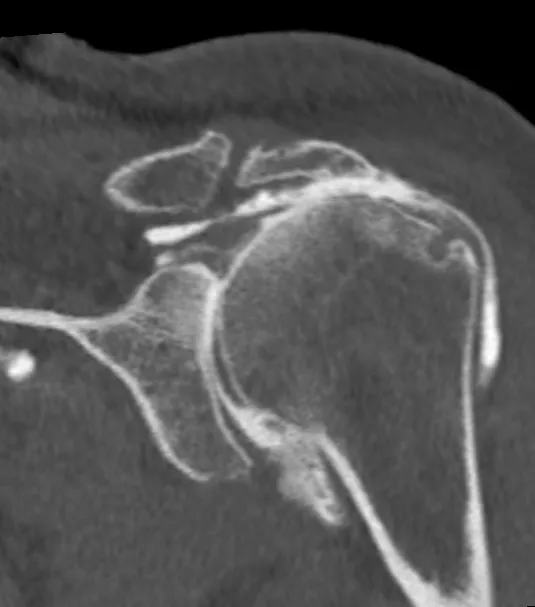

Dans un premier temps des radiographies permettent d'avoir une orientation diagnostic en corrélation avec l'examen clinique du chirurgien. Il s’agit du bilan de débrouillage qui sera complété le plus souvent par un arthro-scanner (plus rarement une IRM).

Si votre médecin généraliste vous oriente vers le chirurgien il pourra, afin de vous faire gagner du temps, vous prescrire ces examens complémentaires (radiographies + arthroscanner). Ceux-ci seront indispensables pour définir précisemment les gestes de réparation qui seront nécessaires au traitement.

Arthroscanner d'une omarthrose secondaire secondaire à une lésion de la coiffe des rotateurs.